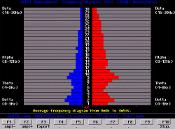

Estas cores representam a média das frequências das ondas cerebrais representando toda a duração do teste. No caso abaixo, de 4, 12 e 4 minutos.

A escala vertical no centro mede a frequência cerebral de 1 Hertz a 30 Hertz em divisões de 1 Hertz.

A distância horizontal para fora do centro mede o poder da onda cerebral.

Também se testa a habilidade do cérebro com a cooperação entre os dois hemisférios a cada ciclo de 2 minutos. Este resultado mostra o equilíbrio entre os hemisférios em cada frequência: Beta, Alpha, Theta e Delta.